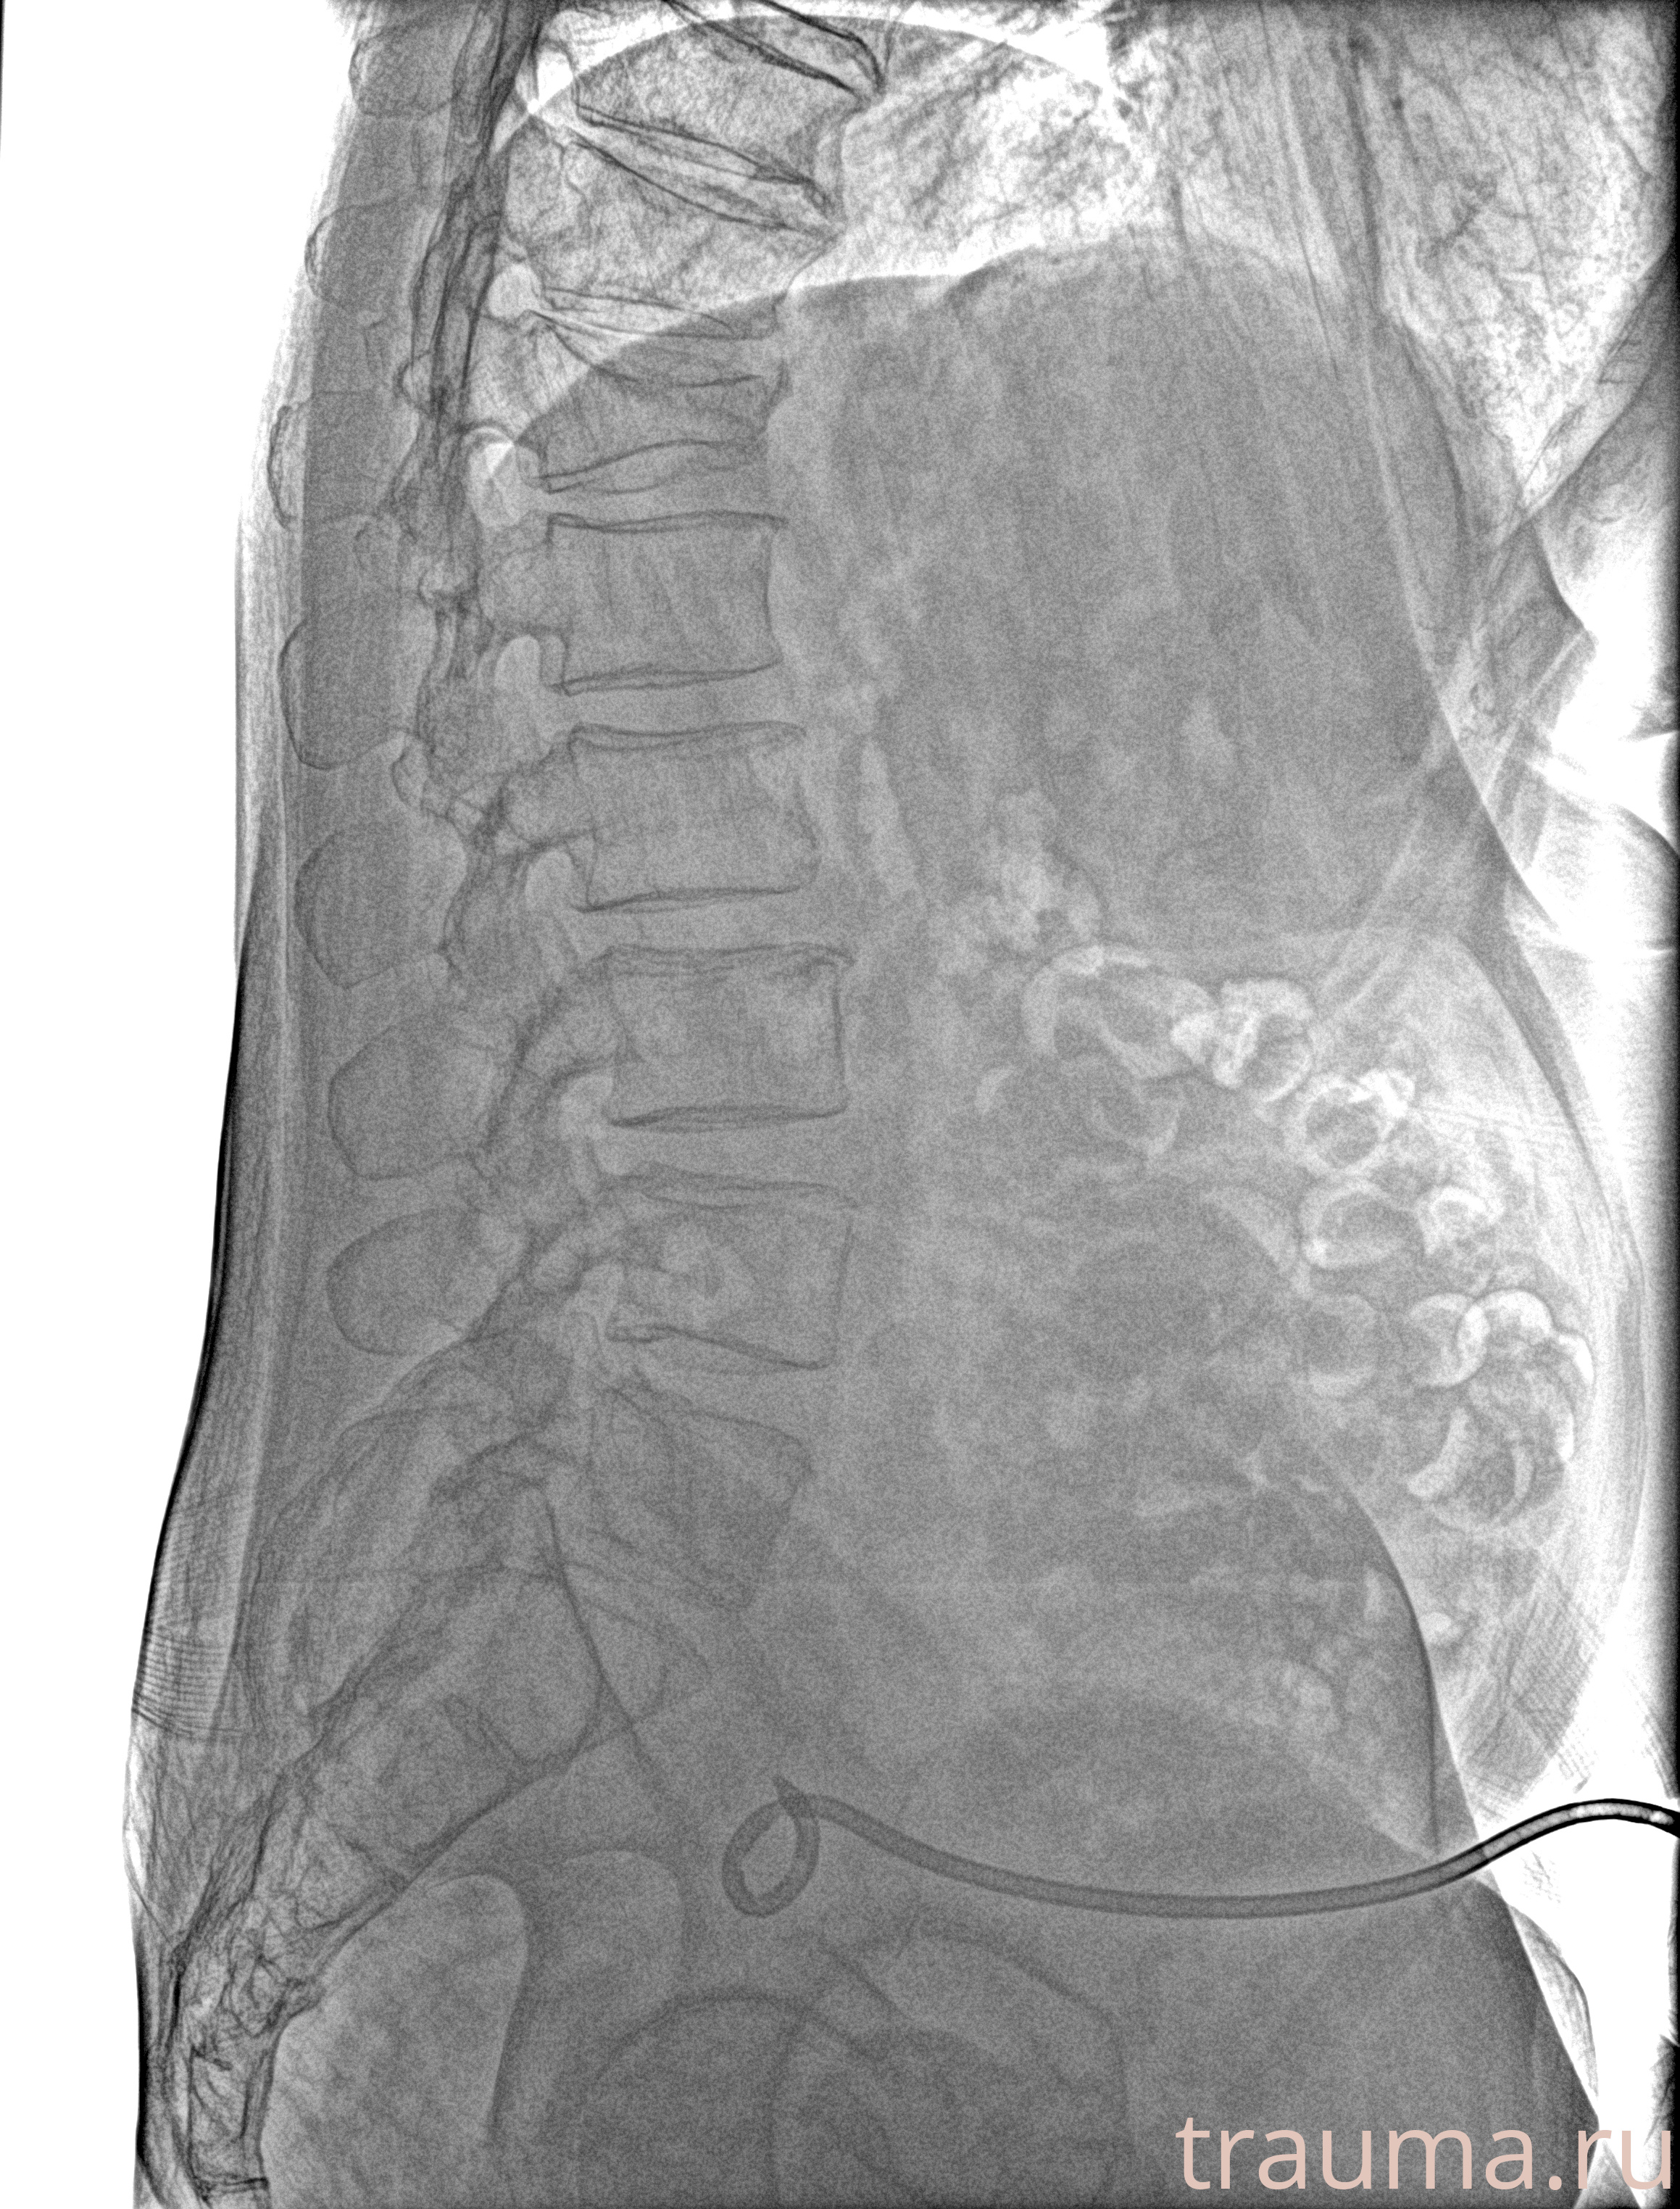

Рентгенограммы

Рентген на дому: по вашему адресу приезжает врач-рентгенолог, травматолог-ортопед с мобильным рентгеновским аппаратом, проводит диагностику травмы или заболевания, делает необходимые рентгенограммы, дает рекомендации по дальнейшему лечению. Получить качественные снимки в домашних условиях возможно благодаря уникальной методике, разработанной МосРентген Центром для института  Склифосовского